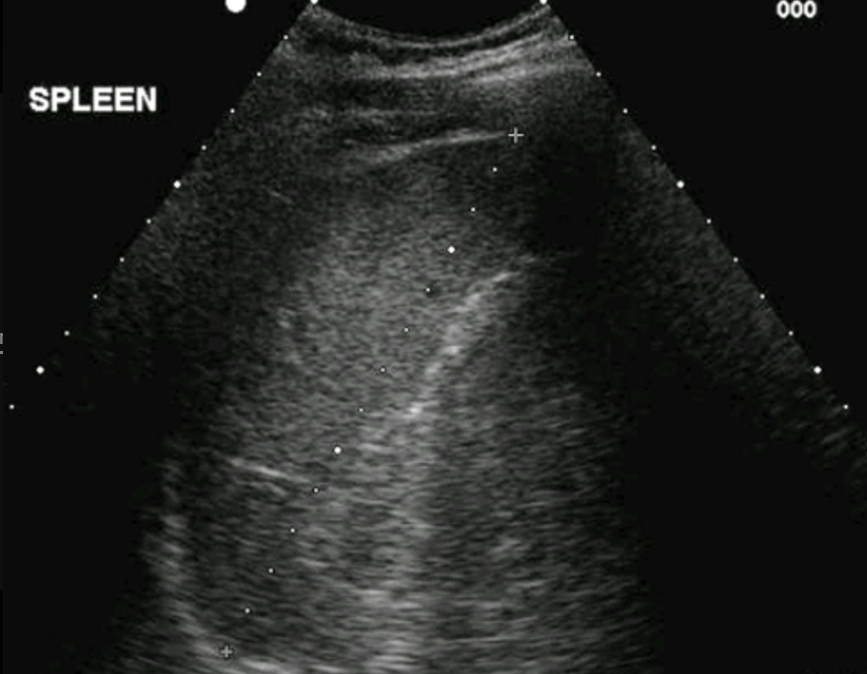

Transverse or long view?

Long